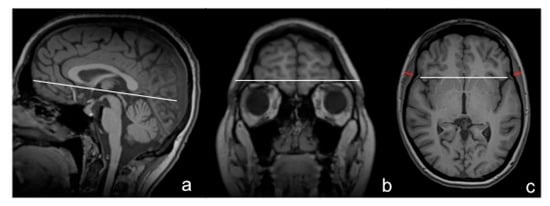

2.2. TMT Measurements